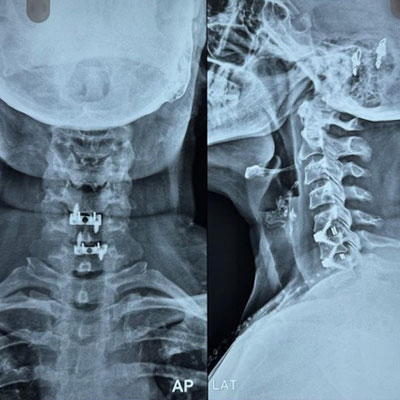

Surgical Highlights